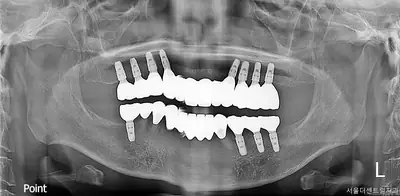

치과 치료를 두려워하는 분들을 위해, 진정요법을 활용한 사례를 소개합니다. 부산에 거주하던 60대 여성 환자가 치아가 많이 손상되어 임플란트와 브릿지 치료를 받았는데, 병원 트라우마와 공포로 어려움이 있었어요. 의식하 진정요법을 통해 깊은 낮잠 같은 상태에서 안전하게 치료를 받았고, 수술 과정도 성공적이었어요. 이 방법은 전신마취보다 안전하고, 환자도 큰 두려움 없이 치료를 마칠 수 있어요. 치과 공포증이 심한 분들도 전문가와 상담 후 진정요법을 고려해보시면 좋겠습니다.